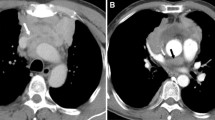

As shown in Table 3, The CEmax of types A, AB, B1, B2 and B3 thymic tumors and thymic carcinoma were significantly different. Overall there was significant difference for CEmax between low risk (types A, AB) and high risk (B1, B2, B3 and thymic carcinoma) subtypes (P < 0.001) (Figure 1). The patterns of contrast enhancement were also significantly different among different pathological types of TETs (P < 0.001) (Table 3).

As shown in Table 2, for the grade of aggressive risk parameter, 63 (29.2%) patients were categorized in Grade I, 57 (26.4%) in Grade II, 21 (9.7%) in Grade III and 75 (34.7%) in Grade IV (Table 2). The relationship between different grades of aggressive risk and WHO pathological subtypes was demonstrated in Figure 3. There was a strong correlation between CT grade of aggressive risk and WHO pathological subtypes (r = 0.801, P < 0.001). Also this parameter could potentially suggest low versus high risk subtypes effectively (Grade I suggested a higher possibility of being low risk subtype, Grade III and IV suggested a higher possibility of being high risk subtype), which might provide additional evidence for subtype prediction. Representative CT images for different grades of aggressive risk were shown in Supplementary Figure 1A–H.